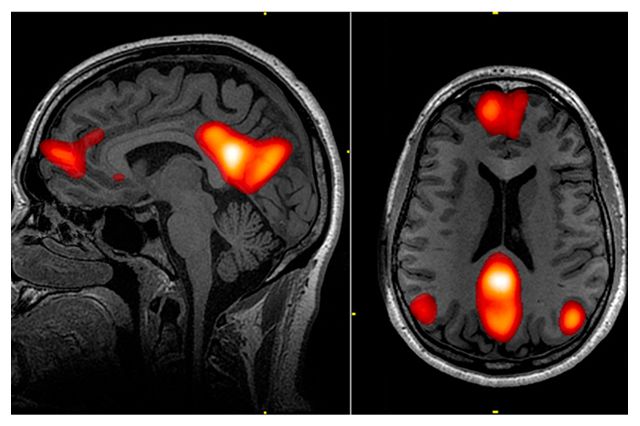

A significant leap forward in GPT Multimodal News and GPT Vision News is the integration of image analysis into the diagnostic workflow. Healthcare is inherently visual—radiology scans, dermatology photos, and pathology slides are as critical as text-based notes. The latest iterations of medical AI are not just reading text; they are analyzing X-rays and CT scans.

For instance, in GPT Applications News, we are seeing pilot programs where models analyze a patient’s history (text) alongside their latest MRI (vision) to suggest potential anomalies. This convergence challenges the traditional architecture of GPT models, pushing the boundaries of GPT Architecture News to accommodate massive, mixed-media datasets without losing inference speed or accuracy.